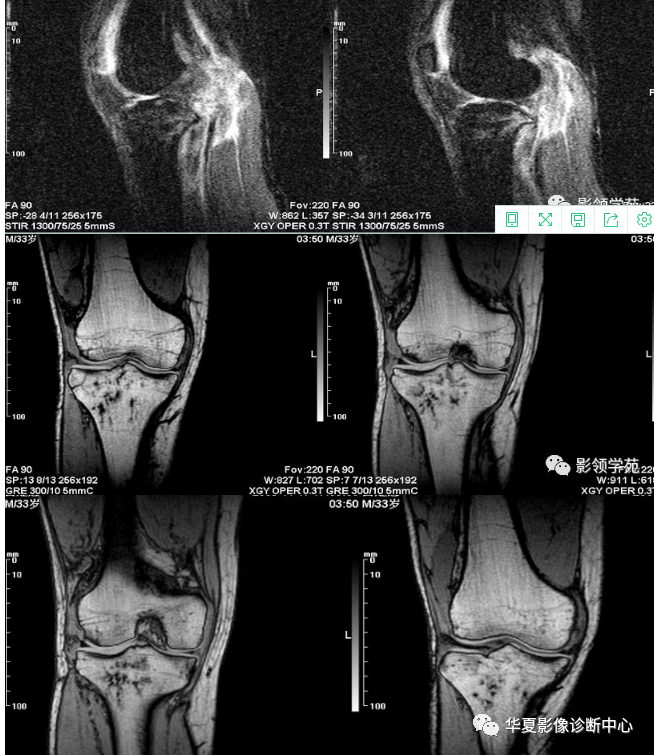

X线平片检查采用Kodak公司的CR成像系统,对患肢行正侧位投照。(图1-2)

CT检查采用SIMENS CT机对患肢行膝关节平扫显示未见明显异常。

骨信号的情况---隐性骨折在低场MRI表现为:T1WI序列上见由关节面向骨干走行的形态各异低信号区,有线状、条状、紊乱低信号,信号强度不均匀;与T1WI低信号改变相对应部位在T2WI上表现为相应形状的高、低混杂信号,且部分低信号周围可见高信号水肿改变。STIR序列图像上病灶呈显著高信号,与信号被抑制的临近正常骨髓形成鲜明对比,分界也较T2WI成像更为清楚。隐性骨折主要病理学改变为骨小梁断裂,无骨皮质中断,并伴有局部骨松质内水肿和出血。无骨皮质中断,尚不足以引起X线衰减系数的明显改变,X线平片无异常征象;CT在显示骨皮质及软组织异常方面明显优于传统X线,特别是三维重建能够有效的评价复杂骨折,骨外伤CT检查应用广泛,但CT对隐性骨折的显示亦极为有限。由外力作用使骨髓局部充血,毛细血管床过渡灌注而致骨髓水肿,水肿时自由水增加,一系列骨组织局部的化学成份变化导致了MRI驰豫时间发生变化,产生MRI信号异常改变。T2WI及压脂序列成高信号影,这信号改变代表着骨髓细胞外液的增多,而细胞外液的增多的程度和数量又决定着水肿所致异常信号的强弱和范围[4]。转组织抑制技术是MRI的一个重要性能,脂肪抑制技术在MRI应用中可以改善组织对比和增加病变显示机会,这样骨髓的脂肪抑制后就不会有任何信号,而隐性骨折线及骨髓水肿的异常高信号就会更加明显的显示出来。膝关节是全身中结构最复杂、最易受损的关节,外伤后常有长时间疼痛、不能负重。如果普通X线或CT检查未检出明显骨折,隐性骨折就容易被临床忽略,患肢若不给予制动,极易发展为明显骨折,或周围软组织的进一步损伤。而MRI其具有多参数、多序列、多方位成像、软组织分辨率高等特点,能清楚地显示膝关节隐性骨折的病变特点及严重程度,且其检查对患者安全,无辐射,因此,MRI检查对X线或CT检查不能解释的症状的患者是必须的,同时可作为定期随访的检查手段。